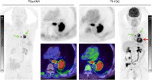

Purpose: FAPI ligands (fibroblast activation protein inhibitor), a novel class of radiotracers for PET/CT imaging, demonstrated in previous studies rapid and high tumor uptake. The purpose of this study is the head-to-head intra-individual comparison of 68Ga-FAPI versus standard-of-care 18F-FDG in PET/CT in organ biodistribution and tumor uptake in patients with various cancers.

Results: A total of 71 patients were studied of, which 28 were female and 43 male (median age 60). In 41 of 71 patients, the primary tumor was present. Forty-three of 71 patients exhibited 162 metastatic lesions. 68Ga-FAPI uptake in primary tumors and metastases was comparable to 18F-FDG in most cases. The SUVmax was significantly lower for 68Ga-FAPI than 18F-FDG in background tissues such as the brain, oral mucosa, myocardium, blood pool, liver, pancreas, and colon. Thus, 68Ga-FAPI TBRs were significantly higher than 18F-FDG TBRs in some sites, including liver and bone metastases.

Conclusion: Quantitative tumor uptake is comparable between 68Ga-FAPI and 18F-FDG, but lower background uptake in most normal organs results in equal or higher TBRs for 68Ga-FAPI. Thus, 68Ga-FAPI PET/CT may yield improved diagnostic information in various cancers and especially in tumor locations with high physiological 18F-FDG uptake.